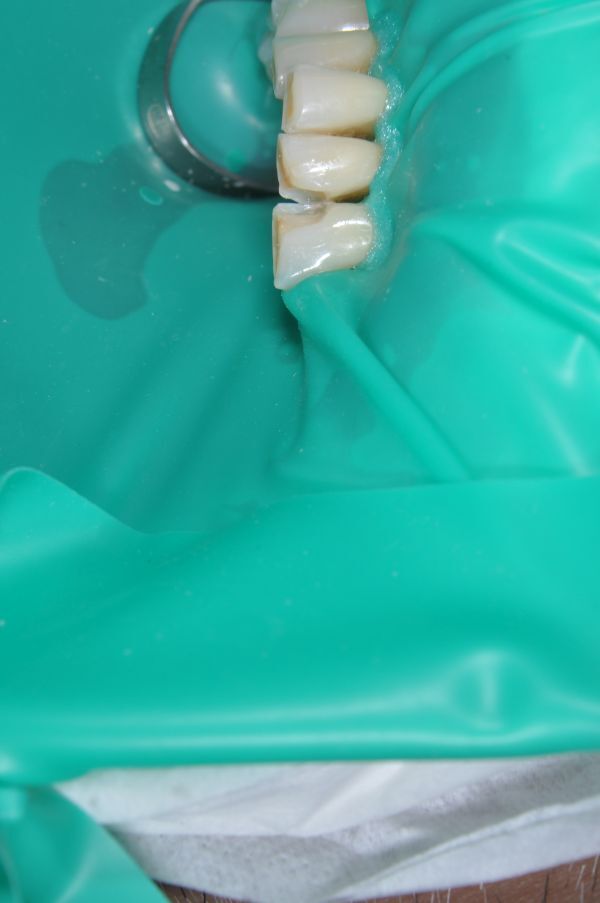

• Изоляция зуба от слюны и влажного дыхания пациента. Качество композитной реставрации зубов ухудшается, поскольку влага отрицательно влияет на пломбы из фотополимерных материалов. При нарушении техники изоляции могут проявиться такие нежелательные последствия¸ как выпадение пломбы либо нарушение краевого прилегания и развитие вторичного кариеса.